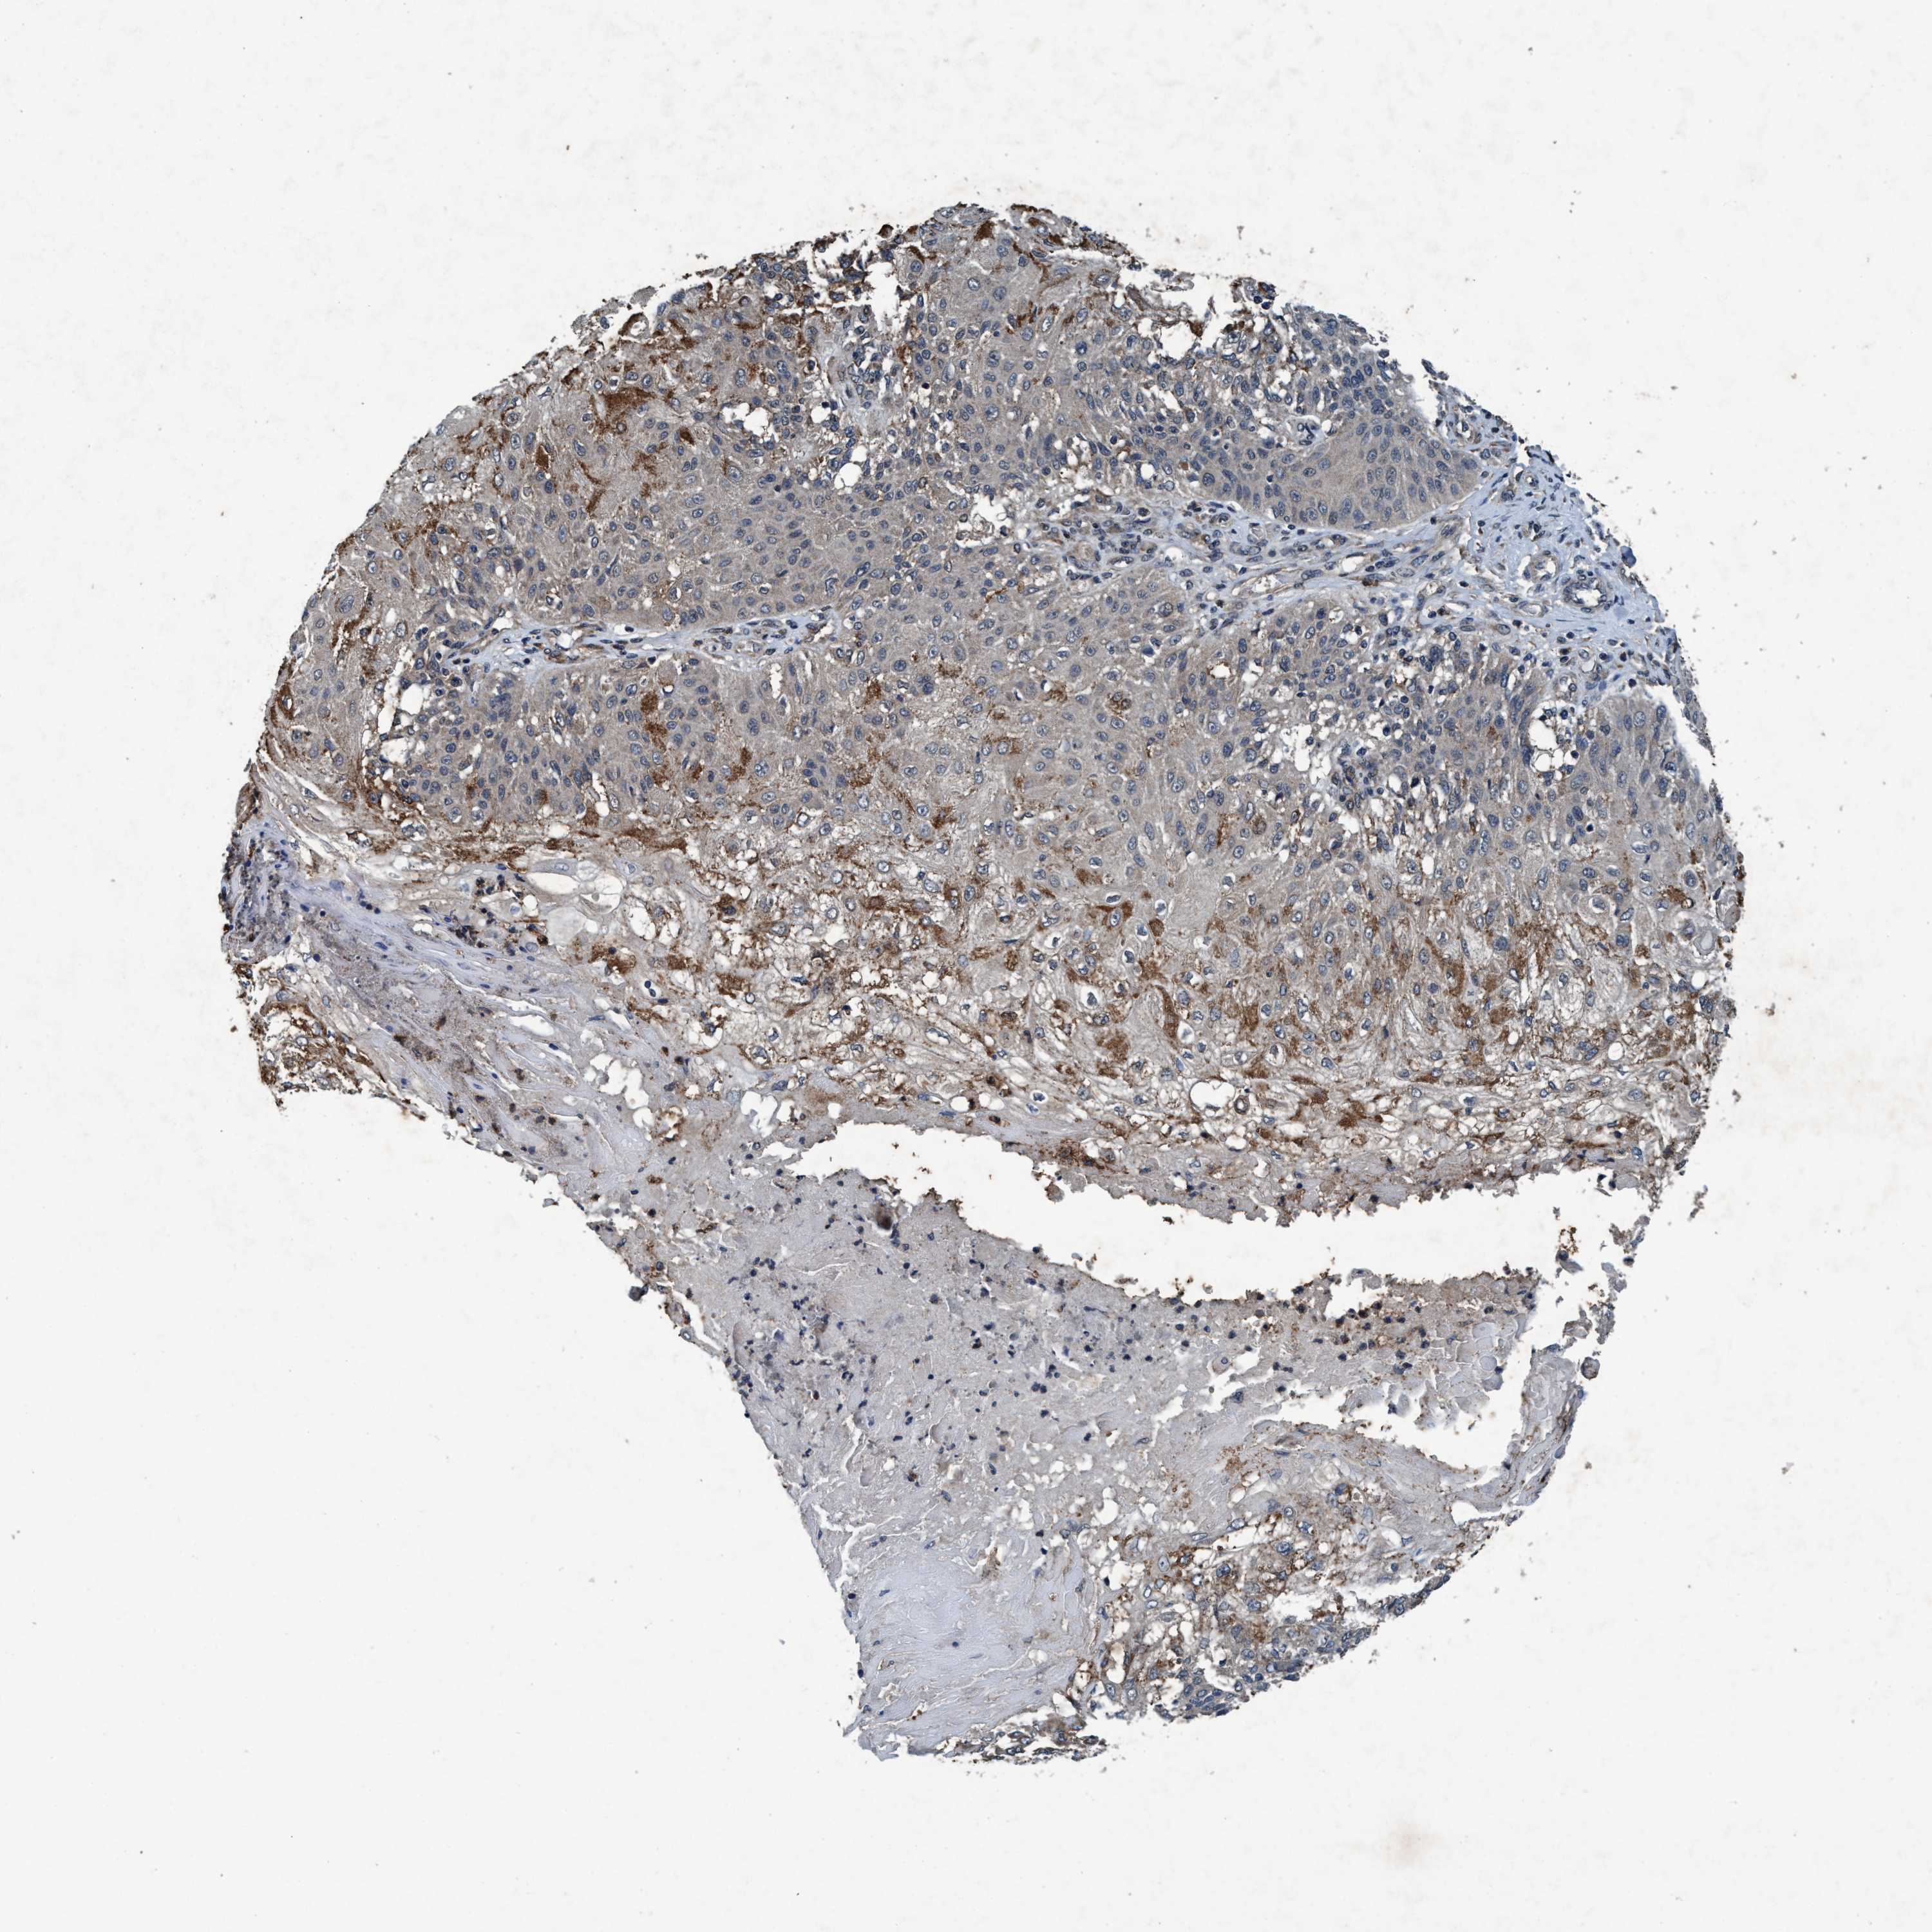

SKIN CANCER - Protein expressioni

A mouse-over function shows sample information and annotation data. Click on an image to view it in a full screen mode. Samples can be filtered based on level of antibody staining by selecting one or several of the following categories: high, medium, low and not detected. The assay and annotation is described here.

Each image is clickable and will lead to virtual microscopy that enables deeper exploration of all samples and also displays staining intensity scores, fraction scores and subcellular localization as well as patient and tissue information for each sample.

Antibody HPA064427

Staining

High

Medium

Low

Not detected

Intensity

Strong

Moderate

Weak

Negative

Location

Nuclear

Cytoplasmic/membranous

Cytoplasmic/membranous,nuclear

None

Basal cell carcinoma

BCC, high aggressive

Squamous cell carcinoma, NOS